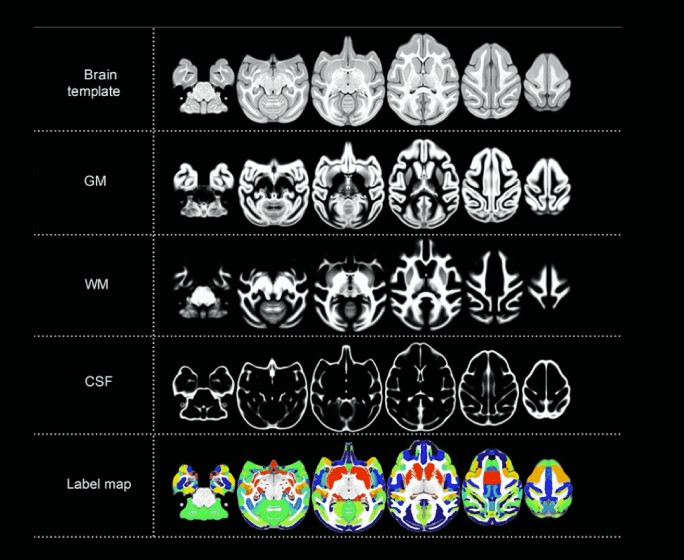

基于联影医疗高端科研型3.0T磁共振、定制猴脑定位仪与线圈,中国科学院昆明动物研究所制作了大样本食蟹猴脑图谱标准化模型,为脑科学领域重大疾病机理研究、治疗及干预技术研究开启无限可能。